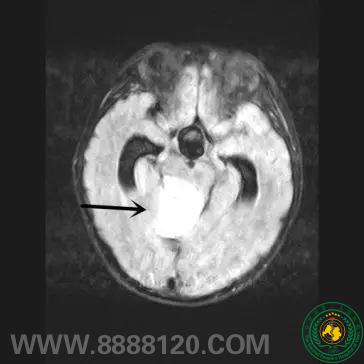

宜宾市第二人民医院 图文